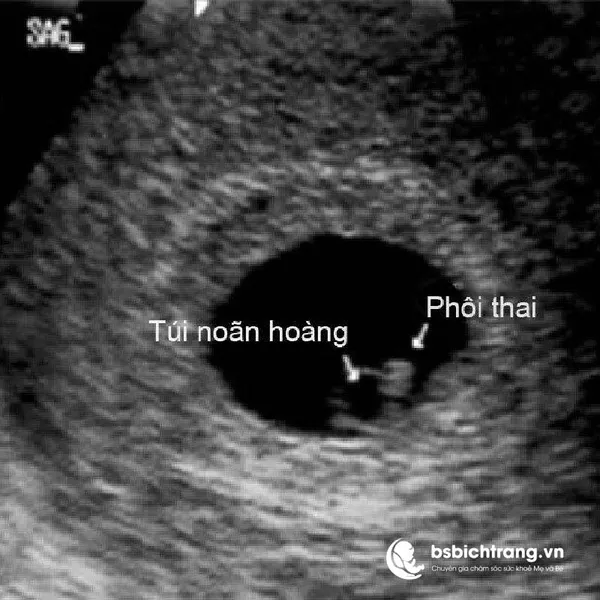

Yolksac là gì? Chia sẻ từ Bs Bích Trang BMT – Chuyên gia chăm sóc sức khoẻ Mẹ và Bé

Khi bắt đầu mang thai, hầu hết các mẹ bầu đều háo hức muốn tìm hiểu thật nhiều thông tin để đảm bảo thai nhi phát triển khoẻ mạnh. Có rất nhiều khái niệm y khoa liên quan đến thai kỳ, từ phôi thai, túi thai, nhau thai đến những yếu tố ít được nhắc đến hơn như túi noãn hoàng. Đây chính là cấu trúc quan trọng cho sự phát triển của em bé trong giai đoạn sớm.